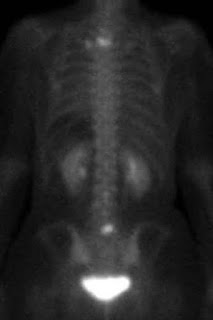

This week, I got to see the actual images from my scans, met with my oncologist, and had a bone biopsy. It's been a busy week and I've had a lot to process. I knew that my current treatment wasn't working and that my cancer had grown, but the images put that in black and white. (The white spots indicate cancer, except for the largest white spot at the bottom of each image. That's just my bladder.)

I've been stable for five and a half years, but it seems my cancer has woken up and is ready to party. I've never been big on the party scene, but I have to say, this is the worst party I've been to in a long time. Don't let Cancer plan your party. I give her zero stars - do not recommend. ;)

Now for the good news: The cancer is still only in my bones. While this can cause me lots of pain, it's not usually life-threatening. My next treatment could shrink these spots or even make them go away! I'm restarting monthly Xgeva injections. Because I had been on the injections for so long (and because they have some scary potential side effects), my time between injections had gone down to every six months. But Xgeva makes my bones strong (hopefully helping to avoid any fractures from these weakened spots) and it also makes them inhospitable to Cancer, so it's a good thing to have it more often now. It's like when the parents come home, catch Cancer throwing her party, and shut it down.